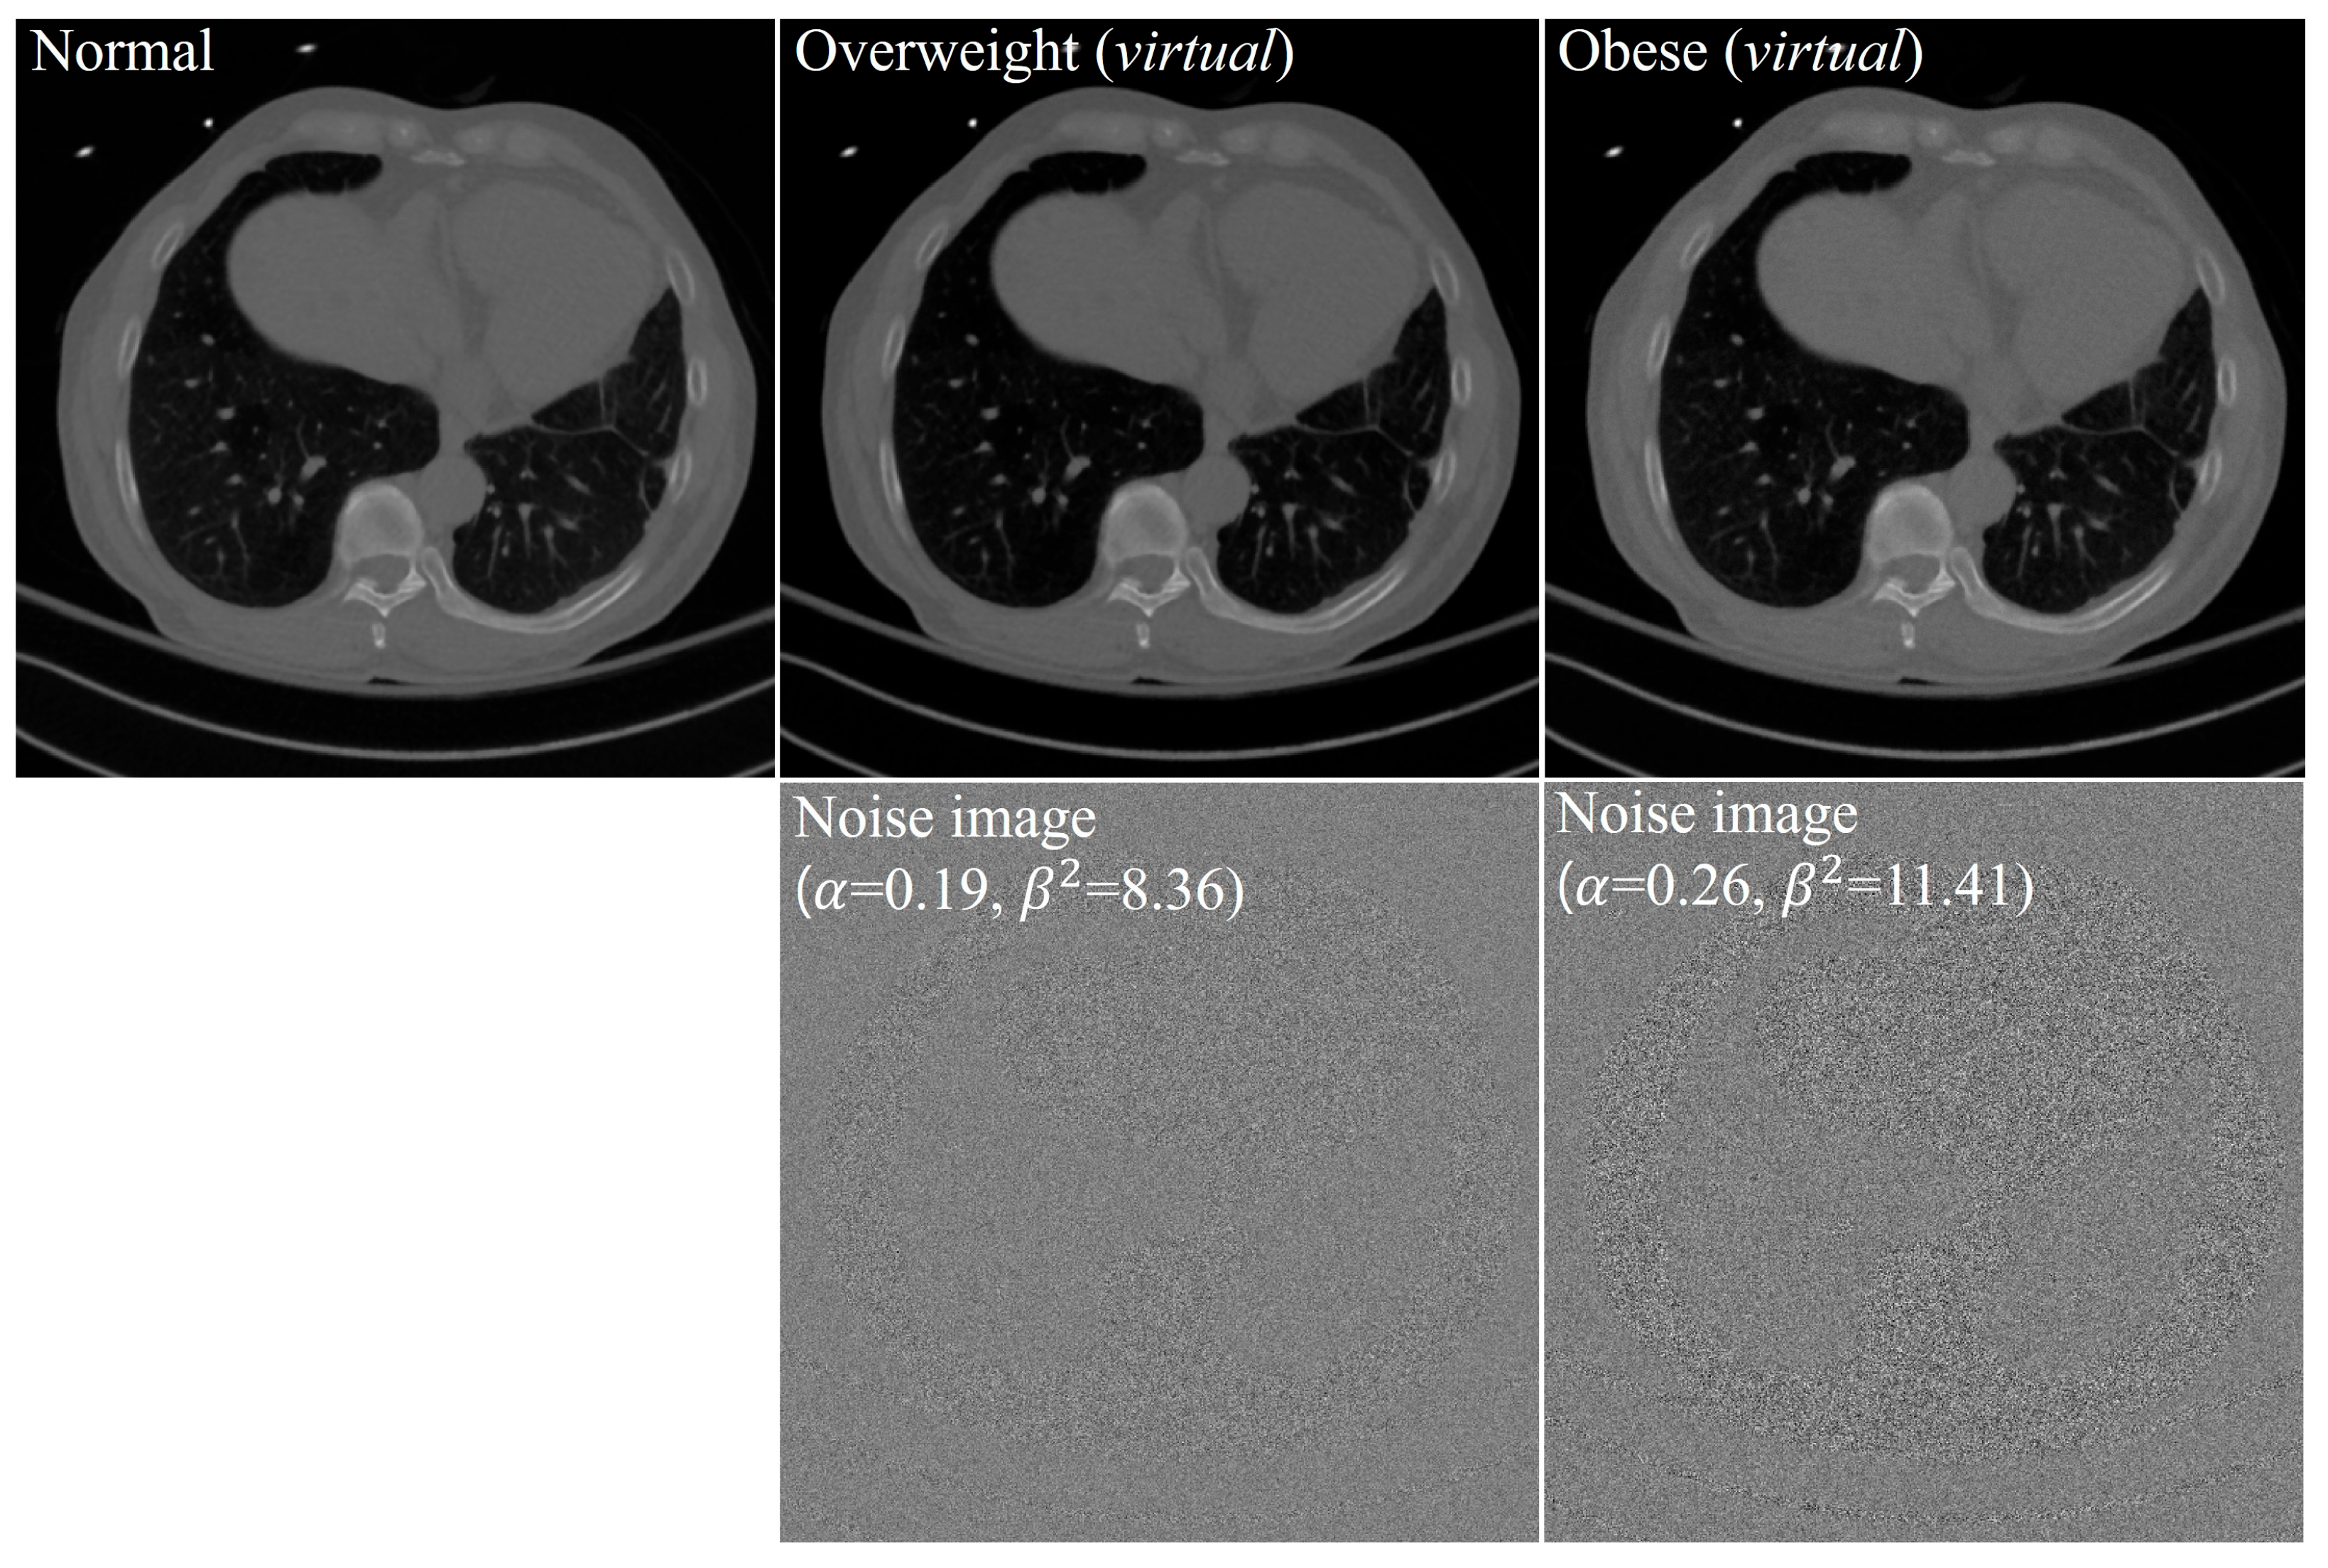

:1. Introduction

2. Materials and Methods

2.3. Image Analysis

| Overweight | ||

|---|---|---|

| Patient 1 | 0.21 | 8.49 |

| Patient 2 | 0.16 | 8.35 |

| Patient 3 | 0.19 | 8.23 |

| Mean SD | 0.19 0.03 | 8.36 0.13 |

| Median | 0.19 | 8.35 |

| Minimum, maximum | (0.16, 0.21) | (8.23, 8.49) |

| 95% CI | (0.12, 0.25) | (8.03, 8.68) |

| Obese | ||

| Patient 1 | 0.25 | 11.36 |

| Patient 2 | 0.19 | 10.29 |

| Patient 3 | 0.27 | 10.42 |

| Patient 4 | 0.33 | 12.27 |

| Patient 5 | 0.27 | 10.67 |

| Patient 6 | 0.23 | 11.10 |

| Patient 7 | 0.36 | 14.04 |

| Patient 8 | 0.39 | 12.60 |

| Patient 9 | 0.33 | 12.42 |

| Patient 10 | 0.38 | 12.57 |

| Patient 11 | 0.16 | 11.31 |

| Patient 12 | 0.15 | 9.74 |

| Patient 13 | 0.17 | 10.22 |

| Patient 14 | 0.21 | 11.62 |

| Patient 15 | 0.17 | 10.59 |

| Mean SD | 0.26 0.08 | 11.41 1.17 |

| Median | 0.25 | 11.31 |

| minimum, maximum | (0.15, 0.39) | (9.74, 14.04) |

| 95% CI | (0.21, 0.30) | (10.77, 12.06) |